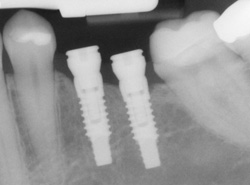

Implants

If you have missing teeth, it is crucial to replace them. Without all your teeth, chewing and eating can destabilize your bite and cause you discomfort. When teeth are missing, your mouth can shift and even cause your face to look older. Implants are a great way to replace your missing teeth.

An implant is a new tooth made of steel and porcelain that looks just like your natural tooth. Your implant is composed of two parts that mimic a tooth's root and crown. The implant's "root" is a titanium steel rod placed into the jaw bone to act as a root. Once the rod is in place, a porcelain crown is attached to replace the top part of your tooth.

An implant is a new tooth made of steel and porcelain that looks just like your natural tooth. Your implant is composed of two parts that mimic a tooth's root and crown. The implant's "root" is a titanium steel rod placed into the jaw bone to act as a root. Once the rod is in place, a porcelain crown is attached to replace the top part of your tooth.

Implants may also be used to anchor dentures, especially lower dentures that tend to shift when you talk or chew. Plus, for patients with removable partial dentures, implants can replace missing teeth so that you have a more natural-looking smile.